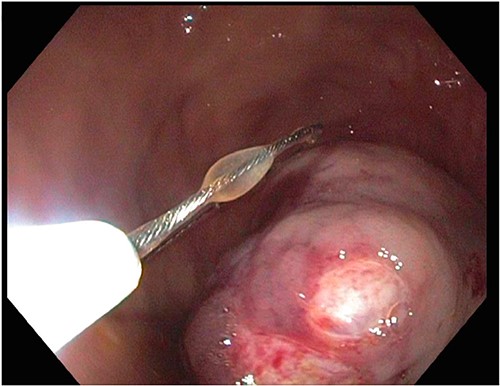

After a few days, the patient was found to have a large volume of melenic stool. A CT angiogram of the chest, abdomen and pelvis was done, revealing a mass in the antrum and pylorus of the stomach with a portion of the stomach pulled into it, consistent with gastroduodenal intussusception without any active extravasation. Repeat EGD showed a large, fungating, pedunculated mass with no bleeding and no stigmata of recent bleeding in the gastric body (Figs. 3 and4) and confirmed gastroduodenal intussusception. The intussusception spontaneously reduced while attempting to push passed the mass. The mass was too large to resect endoscopically. Given these new findings, the family agreed to surgical intervention. An exploratory laparotomy was made, and the patient underwent partial gastrectomy, distal antrectomy and Billroth II procedure. The resected large gastric body mass within the mid gastric body and two nodes were sent for frozen section and immunohistochemical analysis. The pathology report confirmed the mass as a GIST, spindle cell type with no significant nuclear atypia or mitosis, arising from muscularis propria, without mucosal invasion and R0 margins. The neoplastic cells stained positive for CD117 (KIT), CD34 and Desmin (focally). The tumor was T3N0M0 with a low mitotic rate, histologic grade G1 and was deemed low risk (3.6%). The patient was discharged to a subacute rehab with an uneventful recovery.